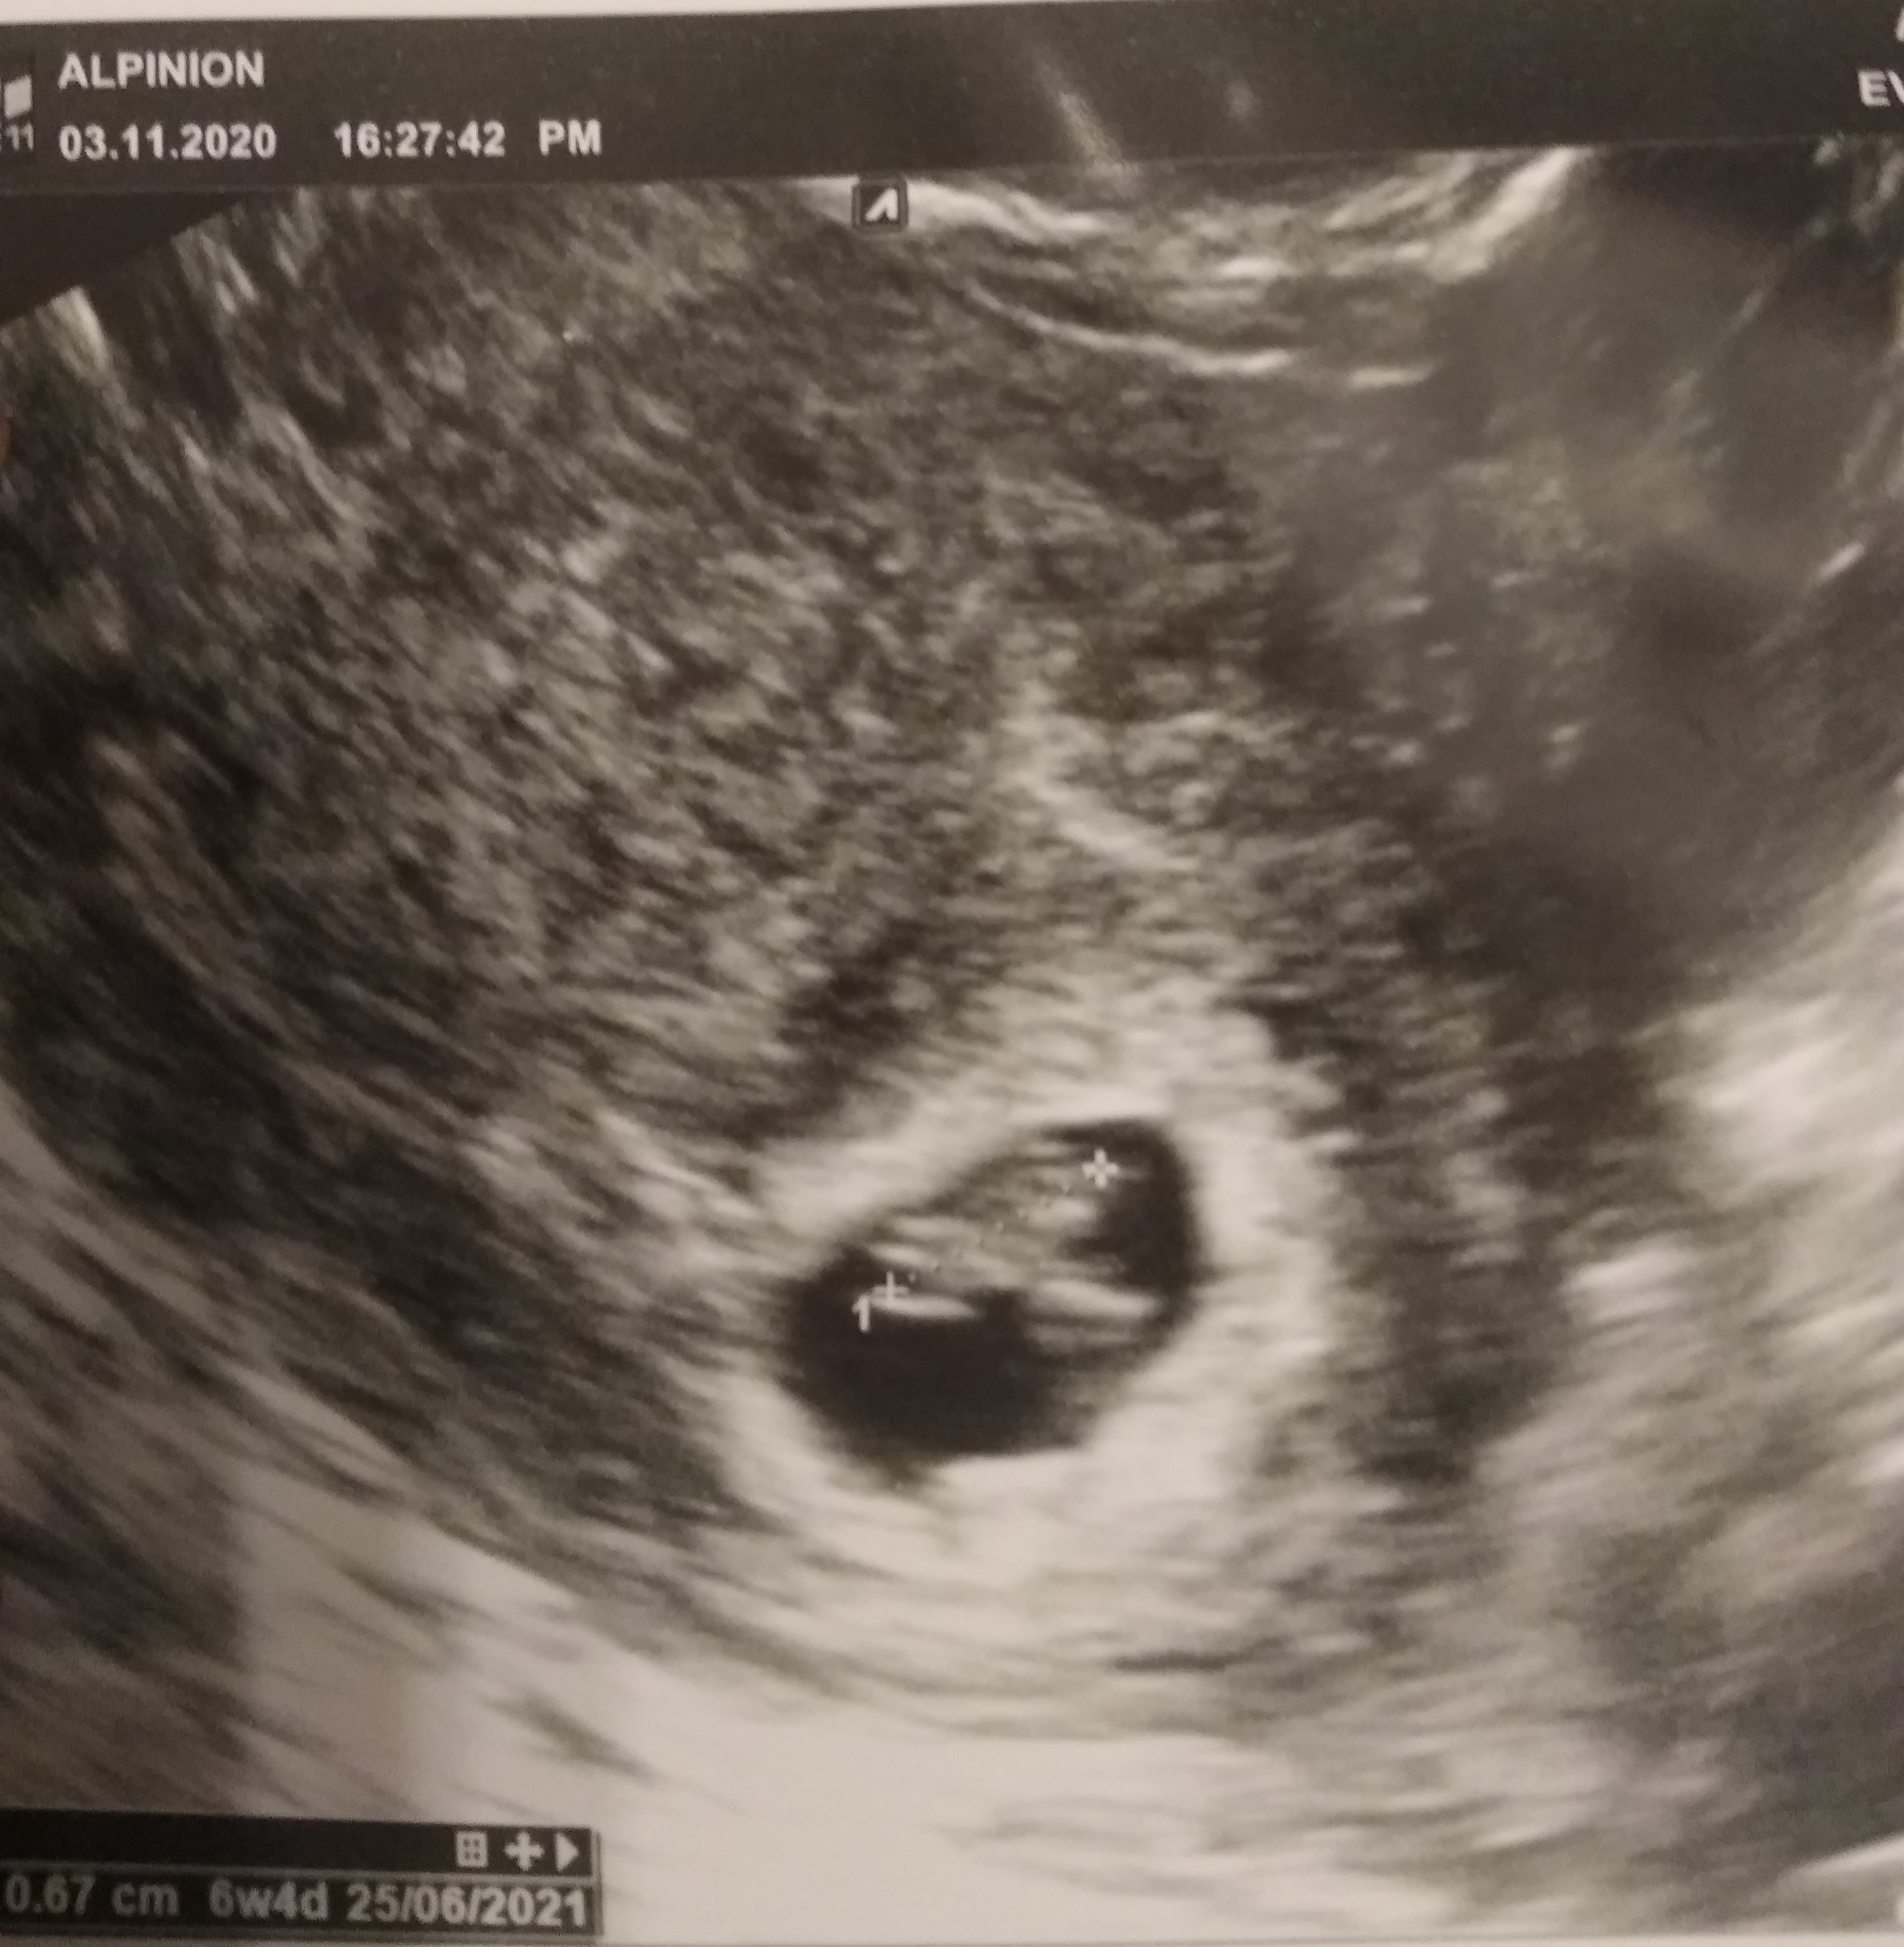

Zobacz załącznik 1196471

Masz dziś 6+4 czy z usg tak wychodzi? Pytam bo też dziś mam 6+4 i się zastanawiam czy w czwartek będzie już coś widać.